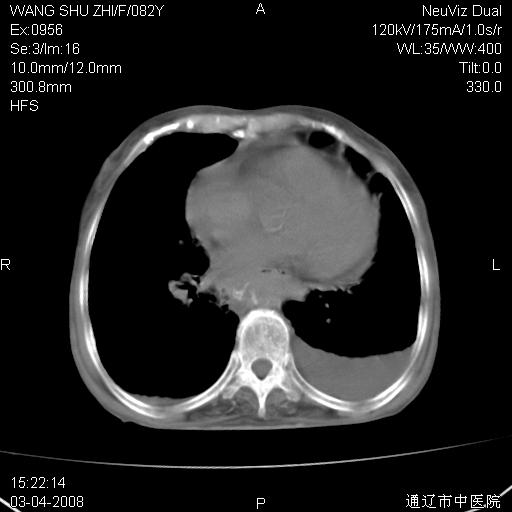

该患者为女性,82岁,既往肺心病、心衰病史。上纵隔影增宽,是否为畸形扩张的血管呢?因该患者年龄太大,又有较严重心脏病,故不适宜做增强检查。

中纵隔肿块最多见是淋巴瘤,而且以hd为多见,呈侵袭性生长,纵隔脂肪间隙消失,再加上心包和双侧胸腔积液,考虑为淋巴瘤(hd)应该说比较准确的。至于说是畸形的血管可能性小,因为畸形血管周围脂肪间隙应该存在。

纵隔淋巴结转移或淋巴瘤;双侧胸腔积液,心包积液。肺窗呢?

病史太简单,年龄太大,首先考虑转移!左侧腋窝亦见肿大淋巴结。

左侧腋窝及纵隔内见多个肿大淋巴结影,左侧少量胸腔积液,心包积液,支持淋巴瘤可能性大,不除外淋巴结转移。